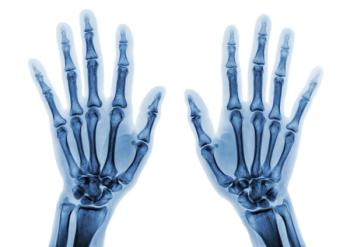

A total of 608 patients from an early RA cohort that had baseline radiographs of hands and feet, as well as at 1, 2, 5, and 8 years, were included in the long-term study.